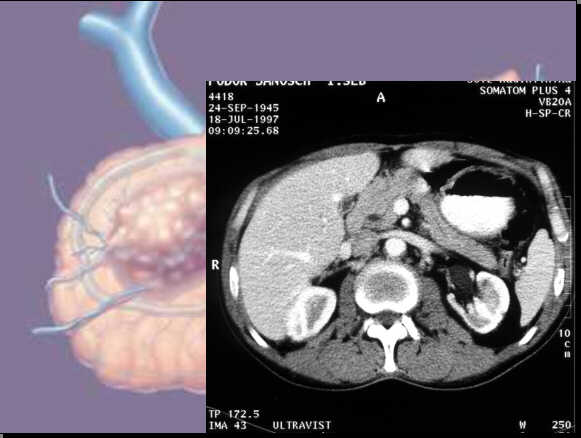

Generally the differentiation is problematic:

Enlarged,

pancreatic head with inhomogeneous parenchyma. Small hypodense

- cystic - lesion in the head: Chronic pancreatitis with pancreatic pseudocyst.

Celiac

trunk.